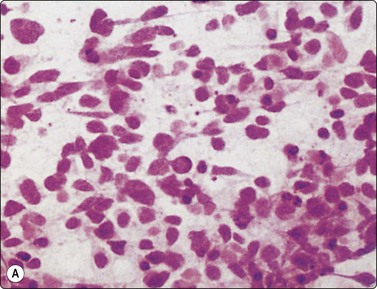

image

Fig. 8.26 Small cell carcinoma

Pleomorphic poorly cohesive cells with little or no cytoplasm; nuclear molding (MGG, HP).

Fig. 8.27 Small cell carcinoma

Small loose cluster showing absence of cytoplasm, finely granular chromatin, inconspicuous nucleoli, nuclear molding and teardrop cells (H&E, HP).

Criteria for diagnosis

Small or medium-sized cells with little or no cytoplasm (larger than in sputum),

Dispersed cell presentation; some clusters, including some small tight groups,

Nuclear molding and engulfment; irregular nuclei,

Uniform finely or coarsely granular nuclear chromatin; small nucleoli,

Tear-drop cells, smeared cells and streaks of nuclear material,

Engulfment of apoptotic bodies,

Numerous mitotic figures.

Cell pleomorphism is so distinctive that a diagnosis of malignancy is seldom in doubt (Figs 8.25-8.27). The most immediate impression is the absence or sparseness of cytoplasm rather than the small size of the neoplastic cell (Figs. 8.26 and 8.27). In fact, the cell nuclei may appear larger than similar cells in sputum and this may mislead one into making a diagnosis of non-small cell carcinoma. This difference in size between sputum and aspirated material is due to degenerative changes and shrinkage in sputum. It is sparseness of cytoplasm rather than size which is the most helpful initial clue in differentiating the lesion from other pulmonary carcinomas.

The combination of dispersal with clustering is also important, especially when other small cell neoplasms enter the differential diagnosis (Fig. 8.25). Lymphomas generally do not display such cell cohesion, although large fragments may be dislodged, and in some cases lymphoid cells may form clusters or packets.

Fragility of nuclei is emphasized by tear-drop cells or streaks of smeared nuclear material,226 and the close nuclear apposition and molding so commonly seen in sputum are also evident (Figs 8.26 and 8.27). Uniform coarsely granular ‘salt and pepper’ nuclear chromatin is also a well-recognized feature of this cancer in other sites, but one point of difference from sputum is the frequency of small nucleoli in aspirated material; they are less commonly seen in sputum. This may also be related to the better preservation of cells removed directly from tumor; small nucleoli are also often seen in bronchial brush material. Mitotic figures are usually easily found.